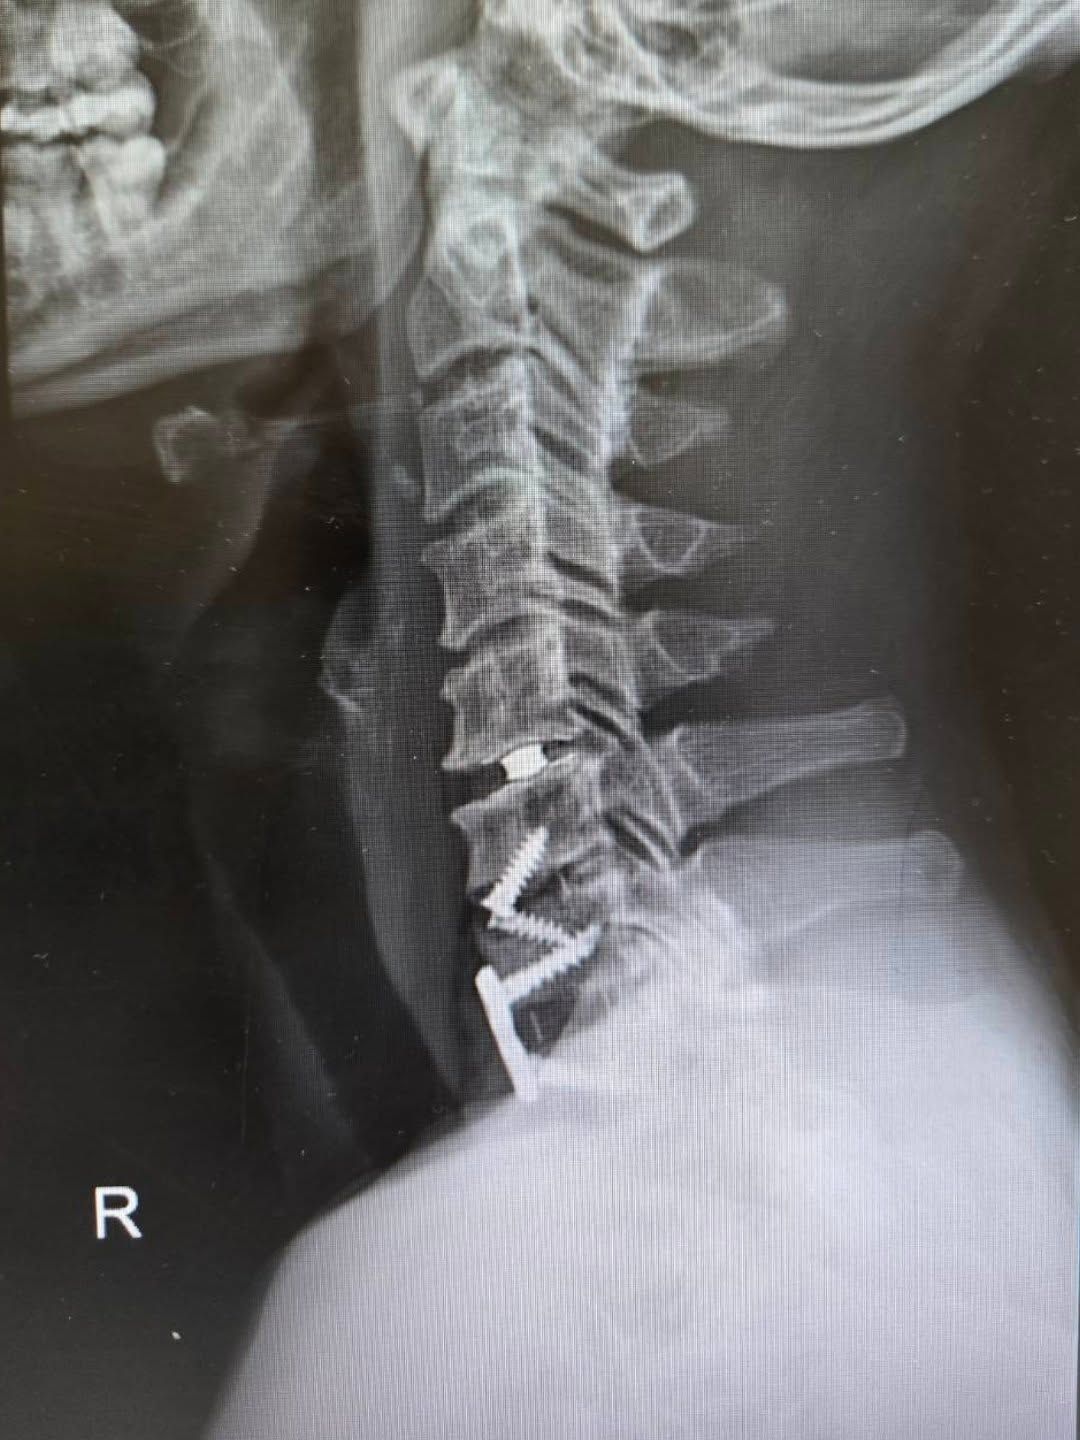

ตูนเปิดเผยว่า ตลอดชีวิตที่ผ่านมาเข้ารับการผ่าตัดมาแล้วถึง 4 ครั้ง โดยแบ่งเป็นที่บริเวณคอ 3 ครั้ง และที่แขนอีก 1 ครั้ง เพื่อย้ายเส้นประสาท สาเหตุหลักมาจากการที่ "หมอนรองกระดูกคอเสื่อม" ซึ่งก่อนหน้านี้เคยผ่าตัดเปลี่ยนมาแล้วหนึ่งรอบ แต่ตรวจพบว่าน็อตที่ใส่เข้าไปเกิดอาการหลวม จึงจำเป็นต้องผ่าตัดด่วนเพื่อนำตัวเก่าออกและใส่เครื่องมือชิ้นใหม่เข้าไปแทน